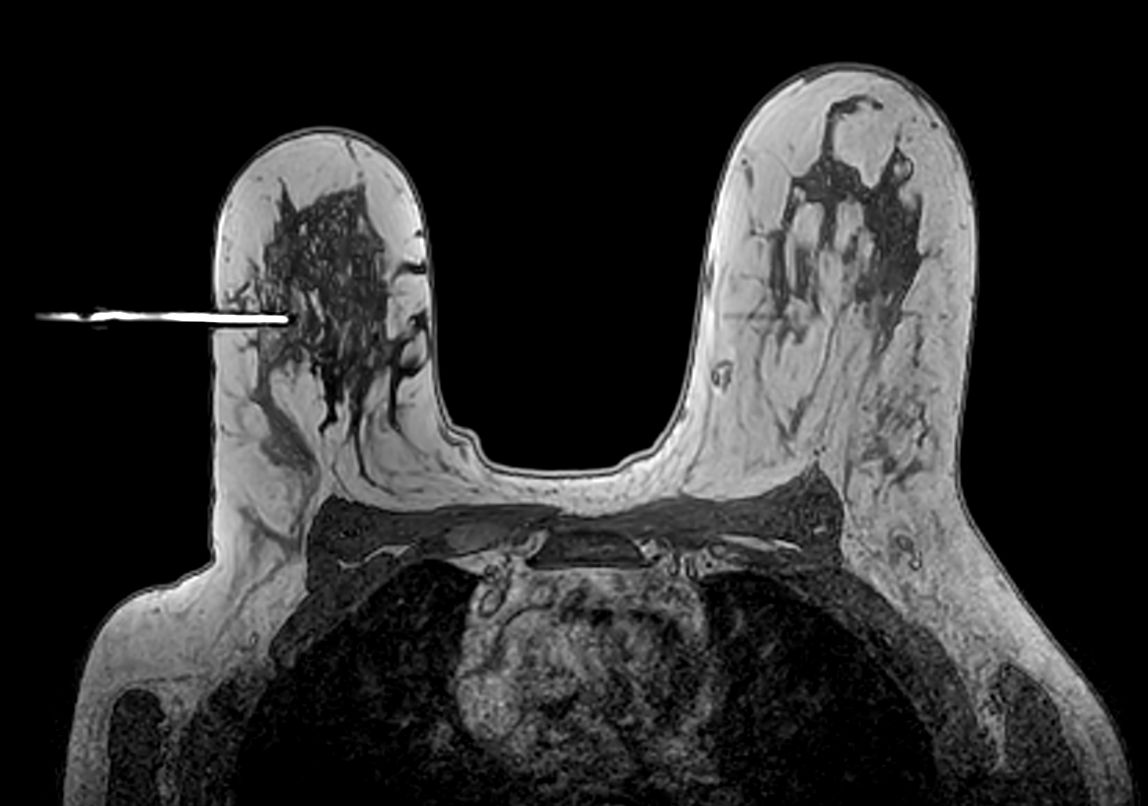

Axial 3D T1w FFE Needle positioning too deep

Axial 3D T1w FFE Needle positioning correct